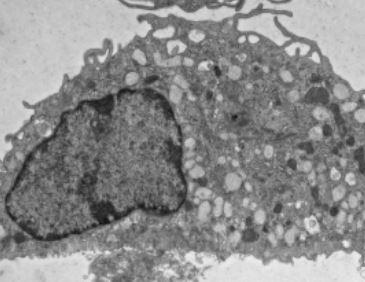

To identify the specific mechanisms at play, Dr. Stappenbeck and colleagues studied mouse models of impaired wound healing consistent with injuries observed in Crohn's patients, finding that D. hansenii levels were significantly higher only within unhealed wounds. They went on to find that the fungus preferentially localized within these wounds to a specific type of immune cell, called macrophages.

They determined that D. hansenii is not broadly pro-inflammatory but rather contributes to disease pathology by increasing the levels of a specific cytokine called CCL5 (chemokine ligand 5). Chemokines such as CCL5 are needed to recruit other inflammatory cells.